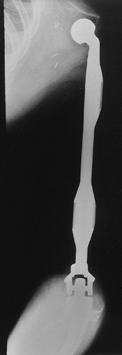

![]() |

|

Figure 126.4. A: Anteroposterior (AP) radiograph of an 8-year-old girl with osteosarcoma of distal femur. B: Lateral radiograph of osteosarcoma. Note the bone destruction and periosteal reaction. C:

AP radiograph after resection of the distal femur. The knee is reconstructed with an expandable custom prosthesis. The articulation is a constrained condylar device. The expansion mechanism is at the top of the prosthesis. D: Lateral radiograph of an expandable knee prosthesis. |